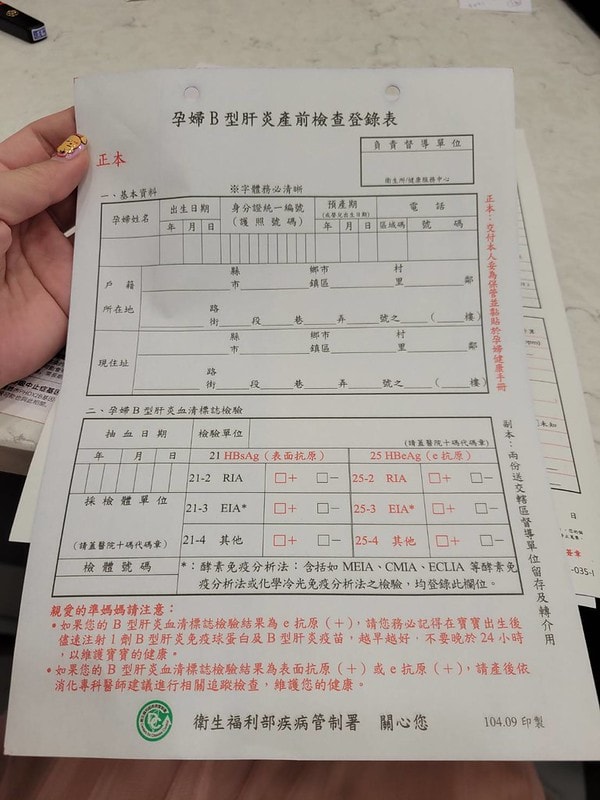

一開始最前面的話會有個健保給付的檢查報告

檢查的是:德國麻疹、AIDS、B型肝炎那些

只要是孕婦這個檢查是不另收費的